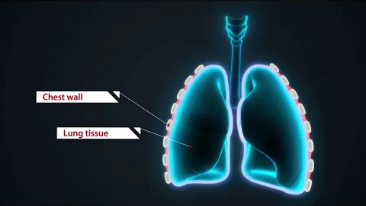

Dank der ZONE Sonography?-Technologie (ZST+) wird das B-Bild des Resona 7 ├╝ber die komplette Tiefe fokussiert, sodass keine Fokuspunkte mehr gesetzt werden m├╝ssen. Die Schall-Lauf-Geschwindigkeit (SSC) wird auf Knopfdruck individuell auf den Patienten angepasst, was die Darstellung von Organen, Grenzfl?chen und Gewebever?nderungen erheblich verbessert. Und dank der fortschrittlichen iFusion-Funktion k?nnen optional die Daten von Ultraschall-, MRT-und CT-Bildern synchronisiert werden.